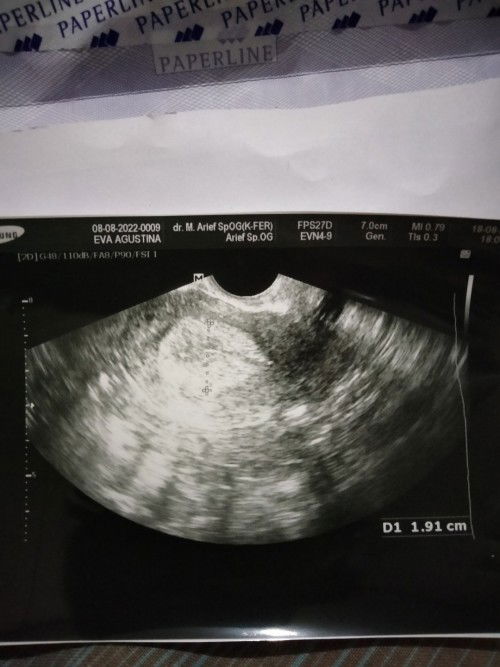

Bunda, saya mengalami flek 3 hr, ternyata dinding rahim saya sudah TDK ada 😭😭 ini kehamilan saya yg ke 2x nya 😭kehamilan pertama saya THN 2019 mengalami secar karena janin berkembang bukan ditempatnya, jd sel telur saya diambil 1 sebelah kiri, skrg hamil yg ke 2 di usia 7w itu cuma sel telurnya 1 dan saya masih penebalan dinding rahim, pas usia 8w trus sy mengalami flek, pas usg kemaren, dokter bilang dinding rahim saya sudah ga ada 😭😭😭😭 ya Allah Bun.. doain saya ya 😭😭🙏🙏

Ass Bun.. saya mau tny apakah ada sprt sy di usia kndungan 6pekan 3 hr msh pnebalan dinding rahim?🥺